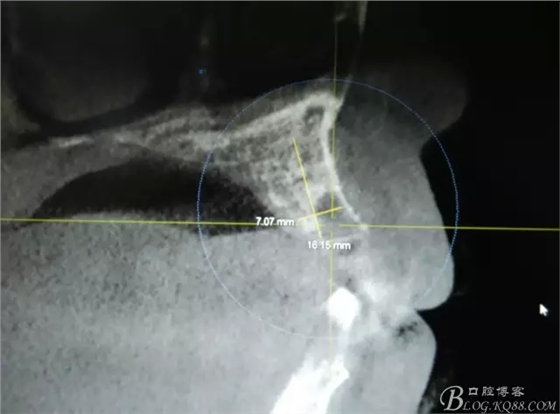

患者、楊xx、男、49歲。主訴:左側(cè)前牙拔除半年,活動義齒修復(fù)四個月,要求種植修復(fù)。??茩z查:21缺失,牙槽粘膜厚度正常。CBCT檢查:高度16mm,寬度7mm.術(shù)前簽知情同意書。

圖2.CBCT的三維成像及縱剖面、水平面影像